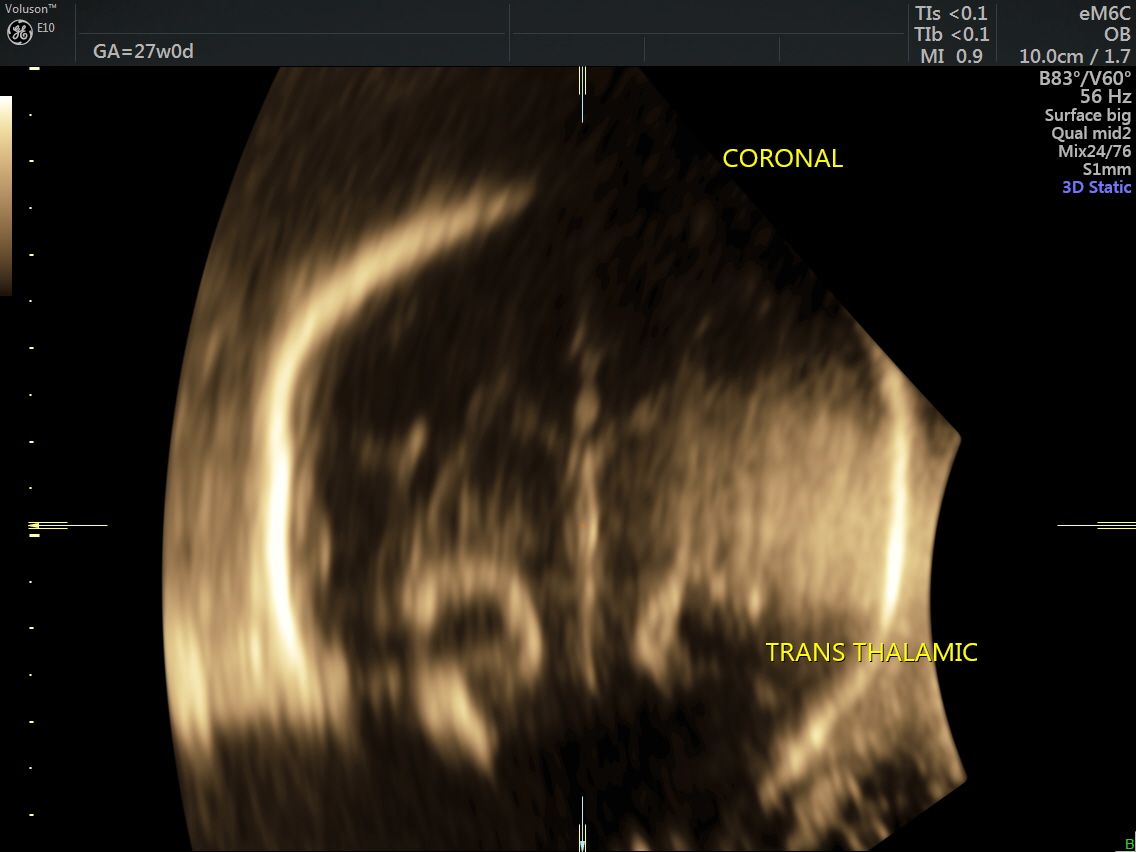

RT AORTIC ARCH_29 Published June 17, 2016 at 1136 × 852 in Rt aortic arch and aberrant left subclavian artery ← Previous Next →